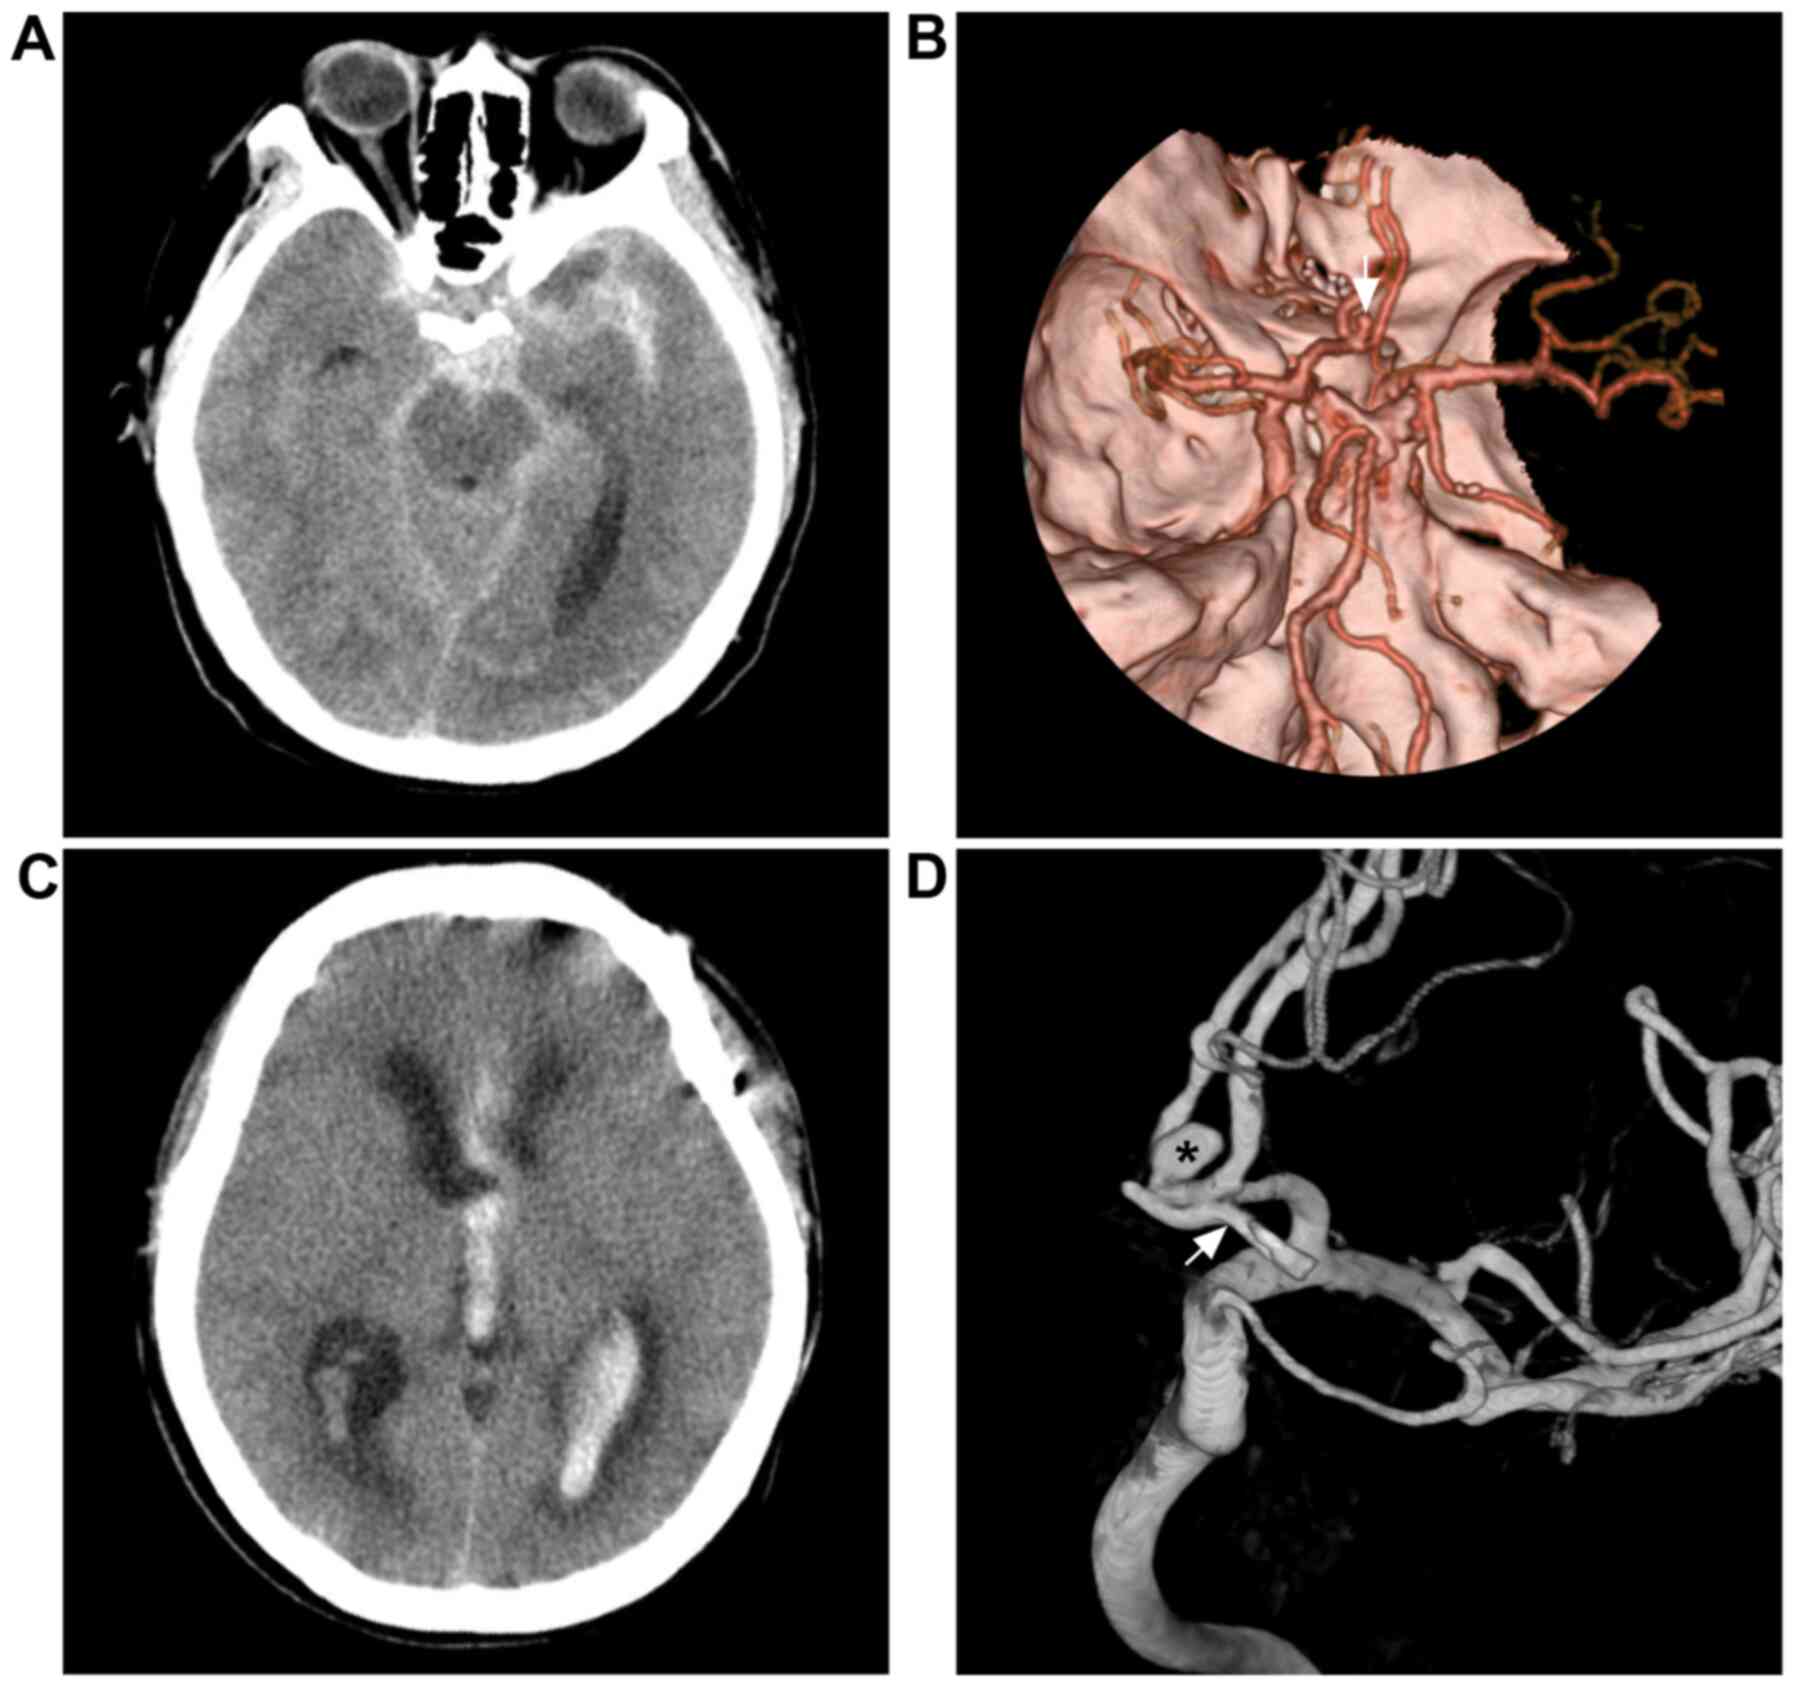

The incidence of intracranial PCRRAs varies substantially, and cases are mainly divided into recurrent cases, following complete clipping, and residual cases, following incomplete clipping (10). The incidence of PCRRAs after complete clipping is 1.8-8.0%, and the annual incidence is 0.14-0.52% (11-14). However, not all aneurysms undergo complete clipping, even when surgeons consider that complete clipping has been achieved (Fig. 1). Of these cases, 5.2-5.9% will have residual aneurysms; the incidence of regrowth is 1.83-2.1% per year, and the total regrowth rate is 12.5-27% (14-19).

Figure 1

Repeated subarachnoid hemorrhage following incomplete clipping. (A) Head CT scan illustrating subarachnoid hemorrhage at the suprasellar cistern. (B) CTA reveals an anterior communicating aneurysm (white arrow). (C) CT scan illustrating intraventricular hemorrhage from re-rupture of the anterior communicating aneurysm recurrent two months after microsurgical clipping. (D) Angiogram illustrating the aneurysm clip (white arrow) under the remnant aneurysm (black asterisk). For the case presented, the surgeon considered that complete clipping had been achieved. CT, computed tomography; CTA, computed tomography angiography.